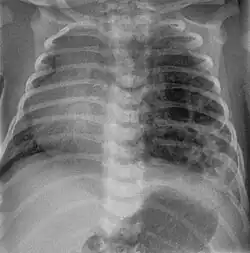

Foreign body aspiration

Foreign body aspiration is a major cause of death in young children due to their underdeveloped swallowing coordination. Young children most commonly ingest toys, coins, or food.[21] On chest x-ray, the most frequent sign is air trapping that can lead to a mediastinal shift. Atelectasis and pneumothorax may also occur in the setting of foreign body aspiration. The diagnosis is made in conjunction with clinical symptoms and confirmed and treated with bronchoscopy.[22]